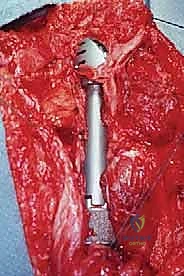

هذه العملية تمثل بصيص أمل ونقطة تحول للكثير من المرضى الذين يعانون من أورام خبيثة (أولية أو ثانوية) في الجزء العلوي من عظم العضد. تهدف الجراحة إلى استئصال الورم بالكامل مع حواف أمان (Margins) خالية من الخلايا السرطانية، مع الحفاظ الكامل على الطرف، والأعصاب، والأوعية الدموية، واستبدال العظم والمفصل المستأصل بطرف صناعي معدني متطور (Mega-prosthesis). إنها شهادة حقيقية على التقدم الهائل في جراحة الأورام الحديثة.

هي مجموعة من أربع عضلات (فوق الشوكة، تحت الشوكة، تحت الكتف، والمدورة الصغرى) تحيط بمفصل الكتف. تلعب هذه العضلات دوراً حاسماً في رفع وتدوير الذراع. أثناء الجراحة، يجب فصل هذه العضلات عن العظم المصاب ثم إعادة ربطها بالطرف الصناعي، وهي خطوة تتطلب براعة جراحية فائقة من الدكتور هطيف.

- تصنيع أو تجهيز الطرف الصناعي: تُستخدم مفاصل صناعية ضخمة معيارية (Modular Mega-prostheses). هذه الأطراف تتكون من قطع متعددة يمكن تجميعها أثناء الجراحة لتطابق بالضبط طول العظم المفقود.

- التخطيط لترميم الأنسجة الرخوة: يخطط الجراح مسبقاً لكيفية تغطية الطرف الصناعي بالعضلات المتبقية، وكيفية إعادة ربط الأوتار لضمان استقرار الكتف.